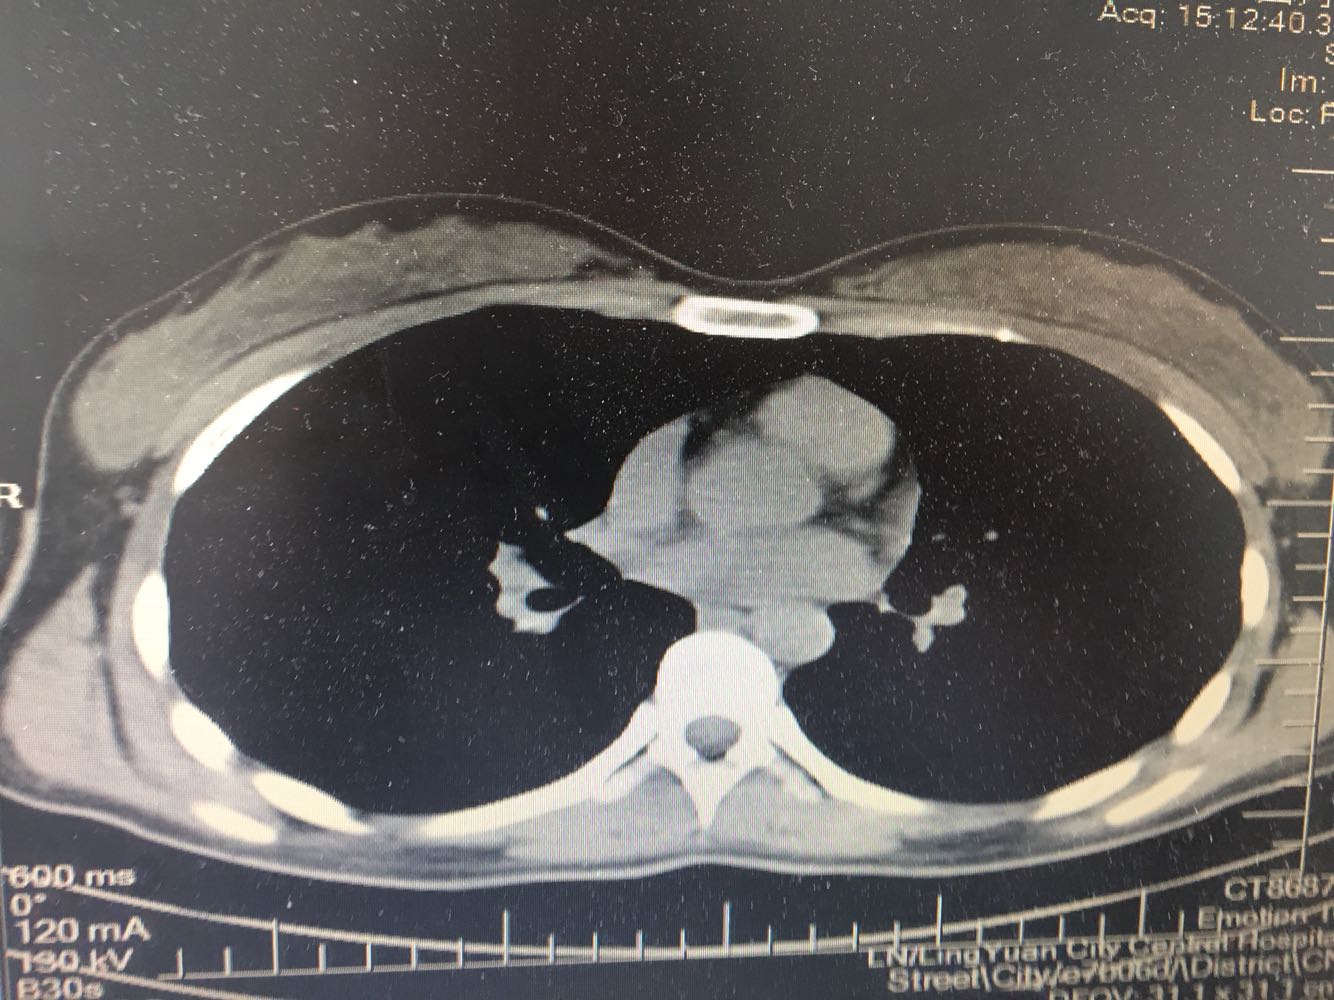

女,26岁,咳嗽1周,咳痰不畅,咽喉痒,口服阿莫西林无好转,昨日发热,体温38.5摄氏度,于门诊查肺CT后以肺炎收入院,病来无盗汗,无咳血,无消瘦及乏力,无头痛,无肢体酸痛,饮食睡眠可,二便正常

神清言明,咽部无充血,扁桃体不大,双肺呼吸音清,无罗音,服软无压痛。

支原体肺炎?肺结核?

支原体抗体1:160,结核抗体弱阳性。支原体肺炎个别可见上叶病变,该患无结核中毒症状,考虑支原体肺炎可能性大,但肺尖为结核好发部位,需要抗炎治疗后复查观察疗效。